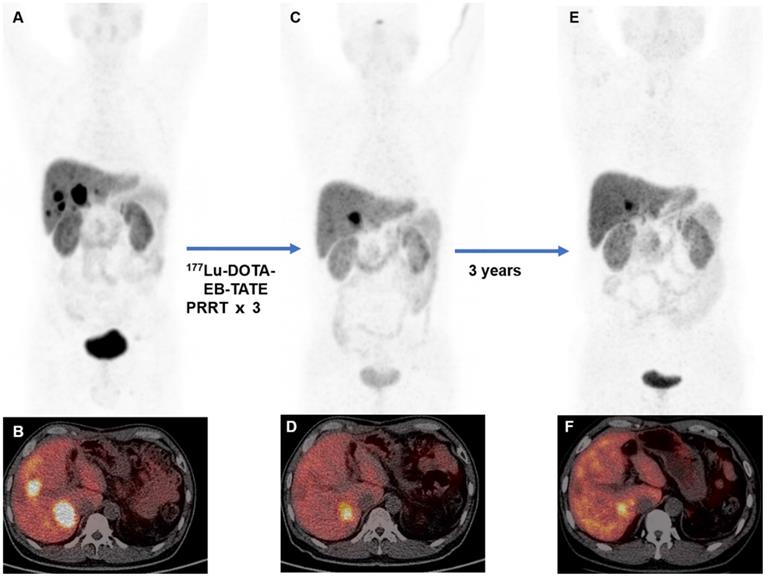

Of the 30 patients enrolled, tumor response assessment based on RECIST criteria was available for 27 patients after 177Lu-DOTA-EB-TATE PRRT. Nine patients had partial response and 14 patients had stable disease, resulting in a response rate of 33.3% and a disease control rate of 85.2%. Four of those 27 patients had progressive disease. Tumor response assessment based on 68Ga-DOTATATE PET/CT was available for 29 patients after 177Lu-DOTA-EB-TATE PRRT. The partial response was seen in 14 patients, stable disease in 11 patients, and progressive disease in 4 patients, with a response rate of 48.3% and disease control rate of 86.2%. According to the primary site, pancreatic NET and non-pancreatic NET showed no statistically significant difference in treatment response referring to RECIST (response rate: 33.3% vs. 33.3%, P = 1.000; disease control rate: 88.9% vs. 77.8%, P = 0.582) and PERCIST criteria (response rate: 58.8% vs. 33.3%, P = 0.264; disease control rate: 94.1% vs. 75%, P = 0.279). Representative cases of 177Lu-DOTA-EB-TATE PRRT efficacy on 68Ga-DOTATATE PET/CT are shown in Figure 1 and Supplemental Figure 1.

A 45-year-old man with metastatic pancreatic neuroendocrine tumor (G1; Ki-67, 1%). The baseline 68Ga-DOTATATE PET/CT (A, MIP image; B, fused PET/CT) showed somatostatin receptor expression in liver metastases. The patient was treated with 3 cycles of 177Lu-DOTA-EB-TATE with cumulative administered activity of 12.4 GBq. Two months post-therapy 68Ga-DOTATATE PET/CT (C, MIP image; D, fused PET/CT) showed partial response. 68Ga-DOTATATE PET/CT at 3-year follow-up showed stable disease (E, MIP image; F, fused PET/CT) with progression-free survival of 43 months from the first cycle of 177Lu-DOTA-EB-TATE PRRT.